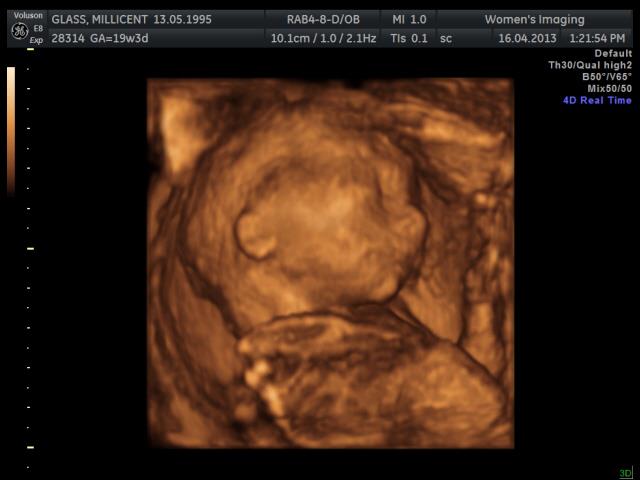

Gender Guesses, :D

Attachment 10727